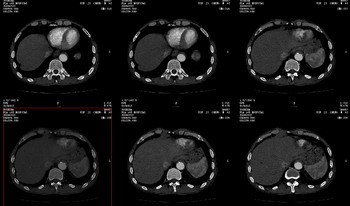

男 62 夜间突然腹痛并向背部放射 ,急诊疑胰腺炎 ,胰淀粉酶正常 ,ct示胰腺未见明显异常,发现降主动脉密度欠均,做主动脉造影示胸腹主动脉半月形低密度充盈缺损,内膜钙化并内移,累及腹腔干致根部明显狭窄,未见明显破裂口。 本人为是不典型夹层,其他人有说是动脉硬化或动脉炎的。请大家发表一下看法。

不典型夹层和动脉粥样硬化、脉管炎怎么鉴别啊 谁有图像最好传上来学习一下

不象夹层,延时扫可鉴别。